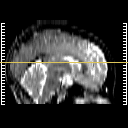

Click on sagittal image to select slice. Click on thin tickmark to change timepoint, or thick tickmark for overlay.